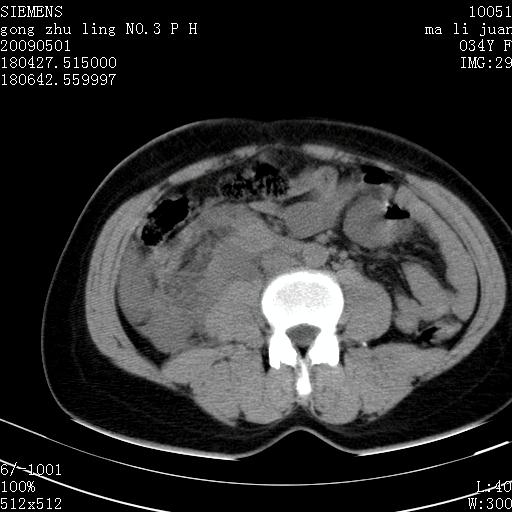

标题: CT19733:右肾碎裂

青年女性,骑摩托车摔伤。

右肾破裂并右侧腹膜后间隙出血。

右肾破裂伴肾包膜下及肾周血肿。